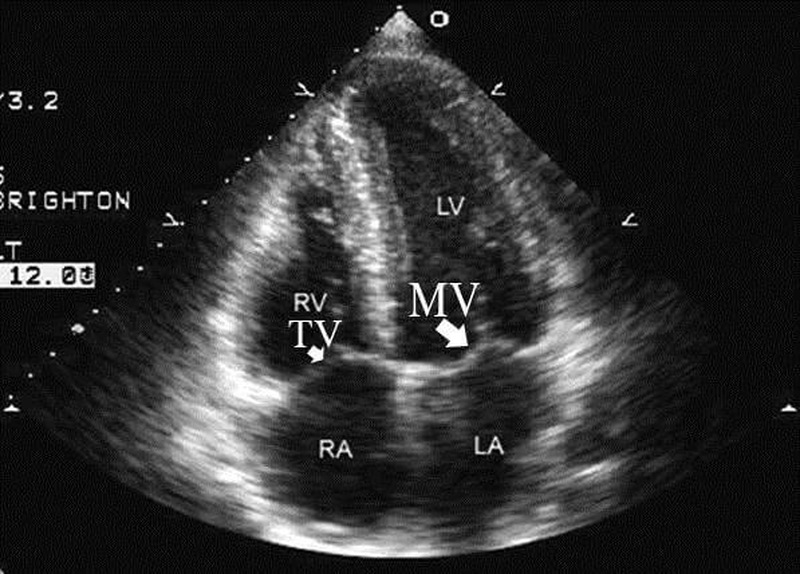

Bạn đã biết về siêu âm tim cơ bản hay chưa? 3 Hình ảnh kết quả siêu âm tim cơ bản